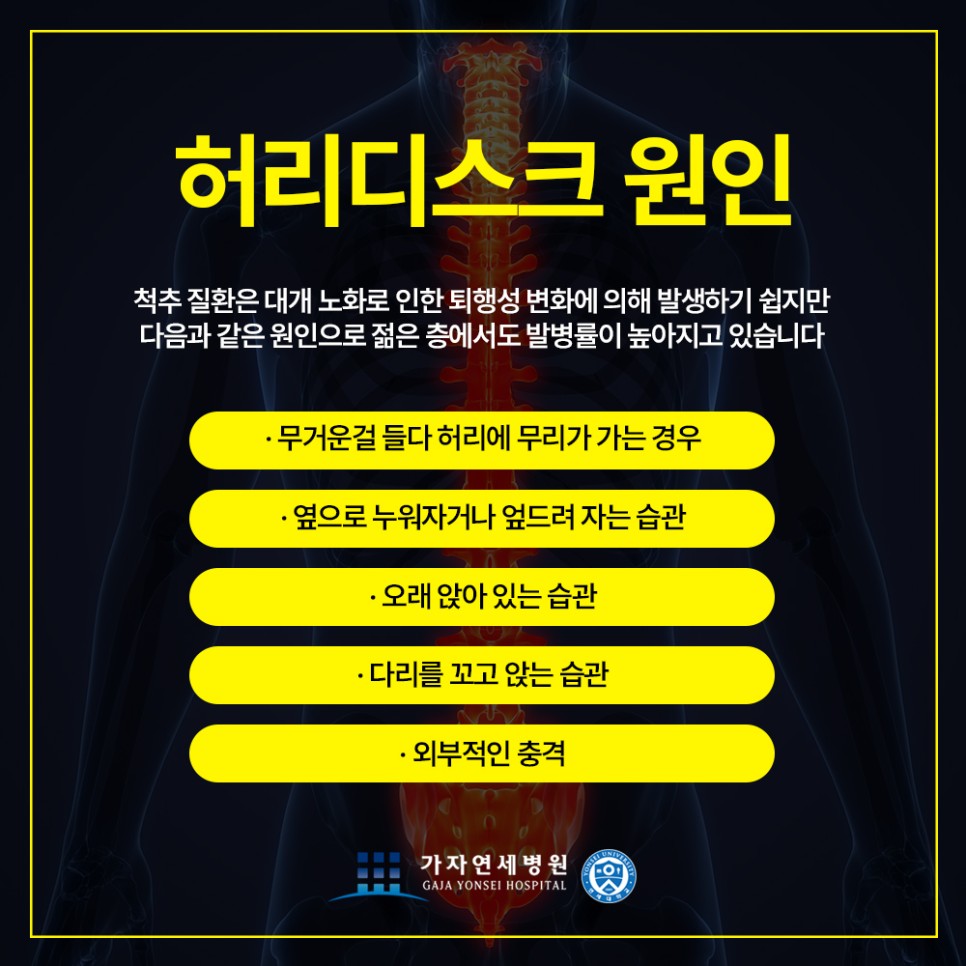

과거에는 노화와 교통사고로 인해 허리디스크를 겪는 분들이 대부분이었어요, 하지만 현대에 들어서는 전자기기와 스마트폰의 사용량이 급증하면서 잘못된 자세를 장시간 동안 지속하고 있는 일이 많아지며 허리디스크가 대중화되었어요. 잘못된 자세로는 대부분 허리를 굽히고 않는 습관, 엉덩이를 앞으로 빼고 않는 습관, 다리를 꼬는 습관 등이 있으며 이러한 자세들은 개선이 필요로 하는 잘못된 자세입니다.